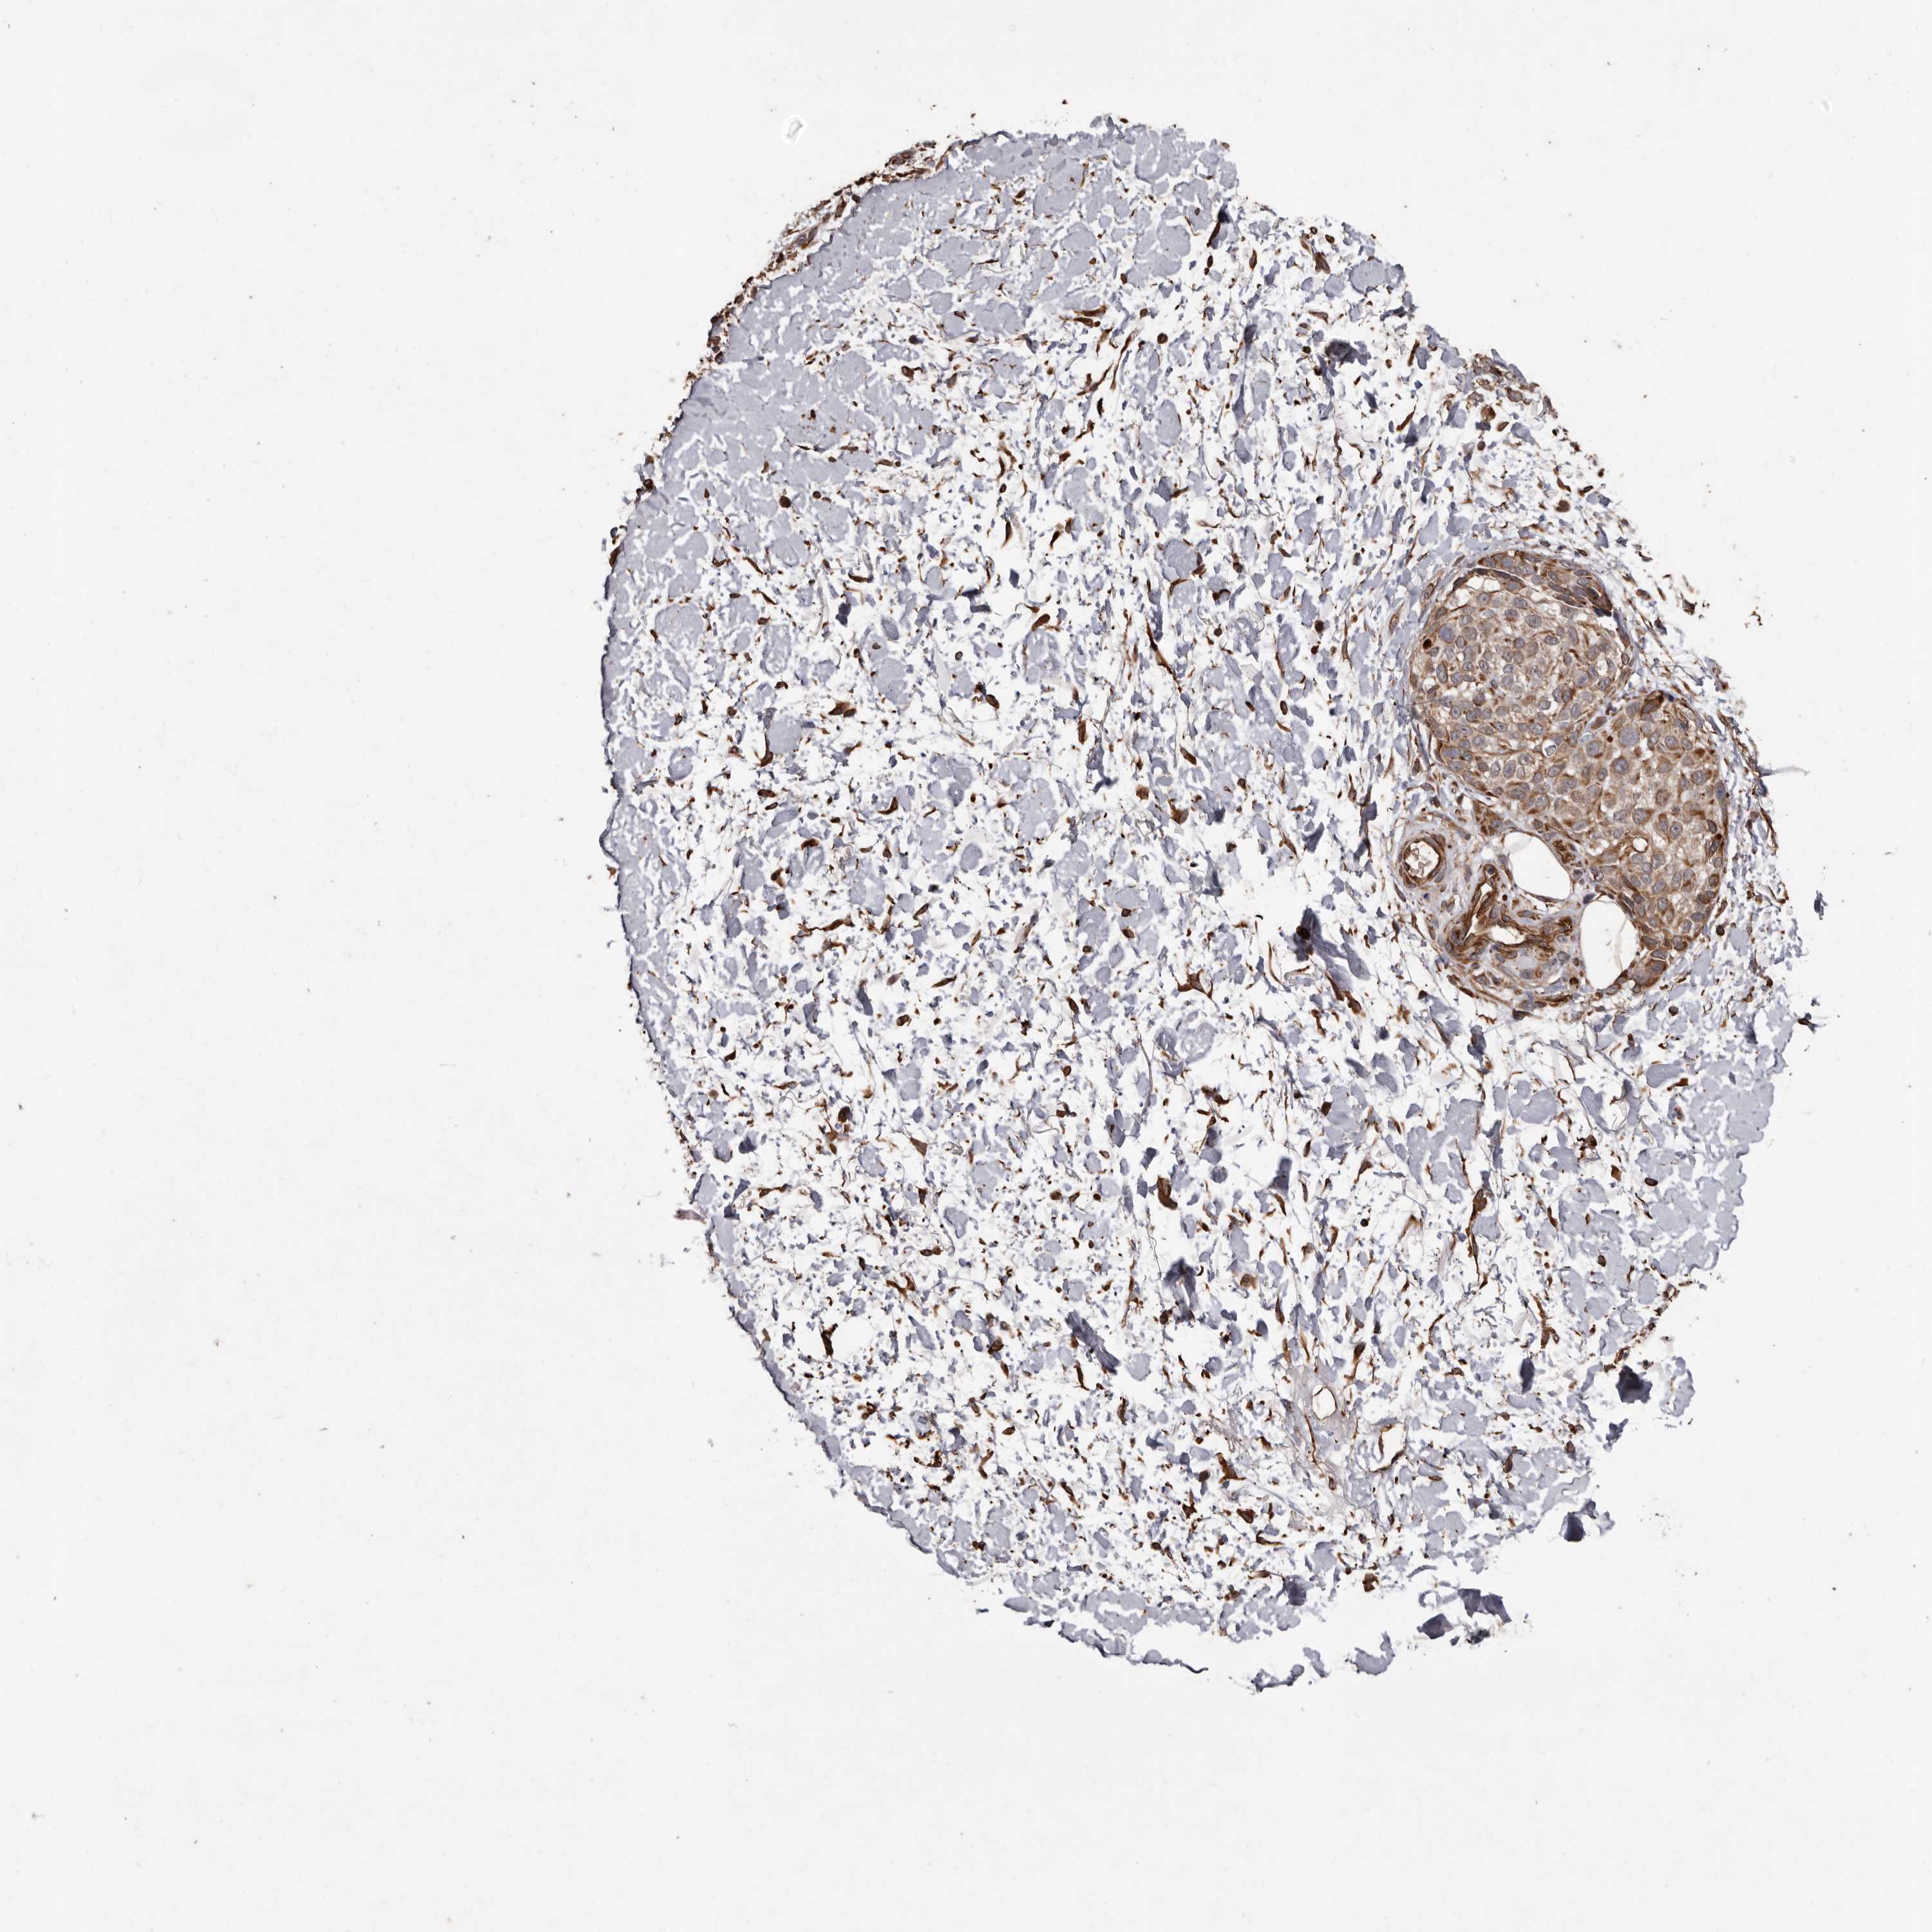

MELANOMA - Protein expressioni

A mouse-over function shows sample information and annotation data. Click on an image to view it in a full screen mode. Samples can be filtered based on level of antibody staining by selecting one or several of the following categories: high, medium, low and not detected. The assay and annotation is described here.

Note that samples used for immunohistochemistry by the Human Protein Atlas do not correspond to samples in the TCGA dataset.

Antibody stainingi

Antibody staining in the annotated cell types in the current human tissue is reported as not detected, low, medium, or high, based on conventional immunohistochemistry profiling in selected tissues. This score is based on the combination of the staining intensity and fraction of stained cells.

Each image is clickable and will lead to virtual microscopy that enables deeper exploration of all samples and also displays staining intensity scores, fraction scores and subcellular localization as well as patient and tissue information for each sample.

Antibody HPA029455

Staining

High

Medium

Low

Not detected

Intensity

Strong

Moderate

Weak

Negative

Quantity

>75%

75%-25%

<25%

None

Location

Nuclear

Cytoplasmic/membranous

Cytoplasmic/membranous,nuclear

Malignant melanoma, NOS

Malignant melanoma, Metastatic site